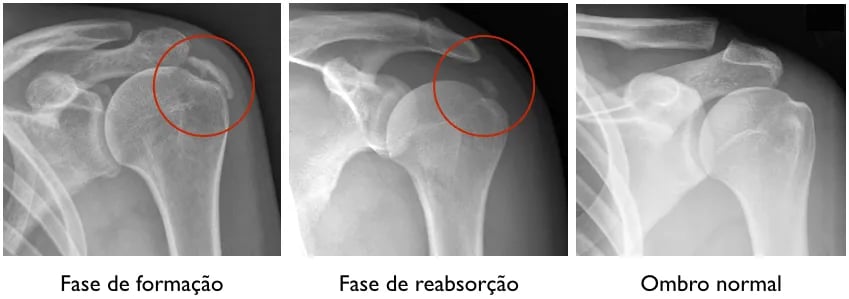

Tendinite calcária é um tipo especial de tendinite que acomete o manguito rotador. Nessa doença, forma-se um depósito de cálcio no interior do tendão. Não se sabe exatamente o que causa essa doença, mas sabe-se que muitas vezes o depósito de cálcio não causa sintomas, e na maioria das vezes o corpo reabsorve o cálcio espontaneamente. Porém, em algumas situações, ela pode ser fonte de dor no ombro.